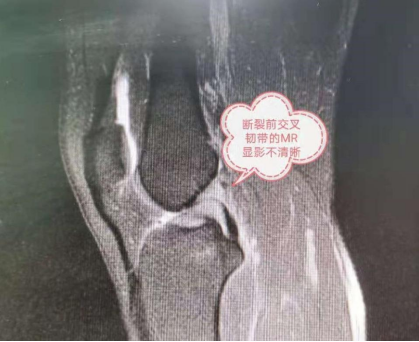

经常进行体育锻炼或者看体育比赛的人一定对“前交叉韧带断裂”这一伤病不陌生,中超广州队球员严鼎皓就曾不幸遭遇这一伤病,度过了漫长的康复时间。